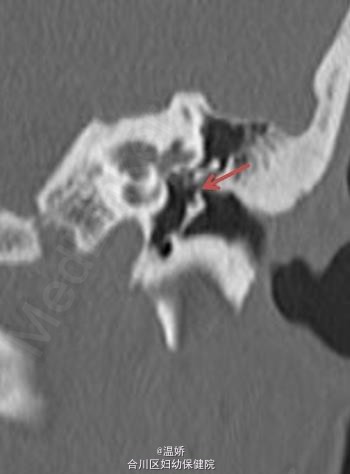

伴先天性耳畸形的范可尼贫血患者 1 例

先天性耳畸形

患者,女性,25 岁,范可尼贫血伴听力丧失。